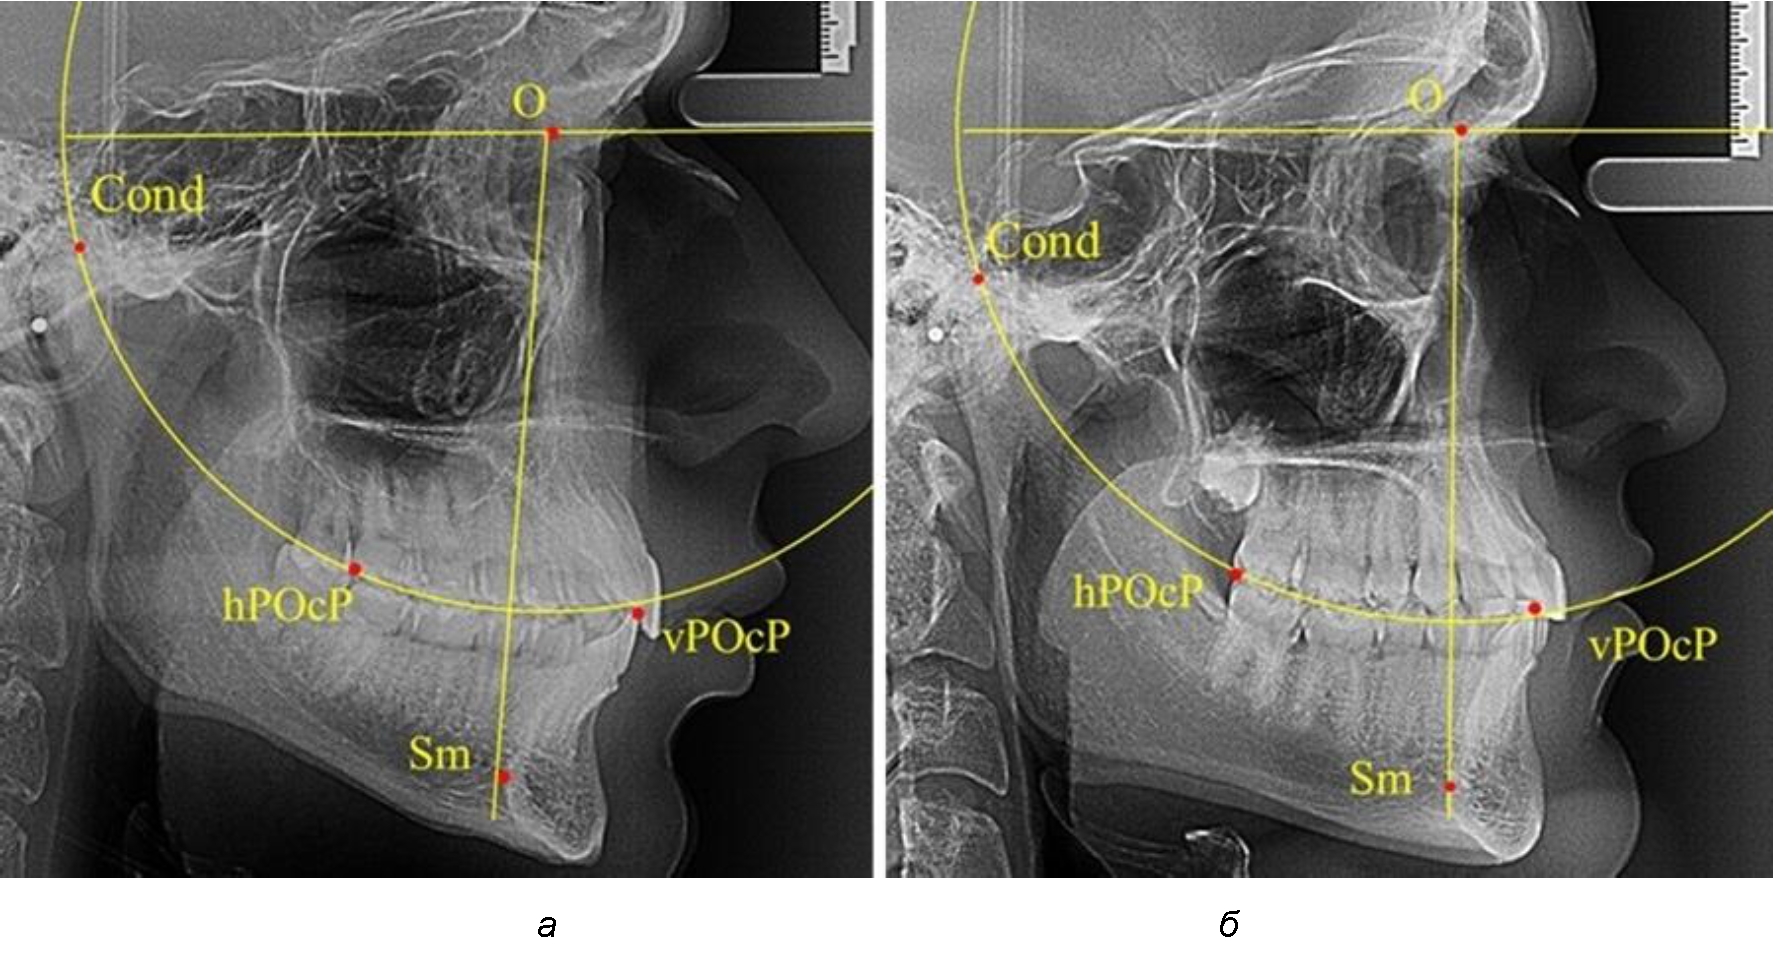

В группе рентгенограмм с ретрузионным положением резцов также проводилось распределение на подгруппы с учетом широтных размеров подбородочного выступа.

Анализ результатов показал, что практически при всех вариантах подбородочного выступа в данной группе исследования первые премоляры, как правило, располагались либо на стресс-оси Bimler, либо позади. Рентгенограммы пациентов с ретрузионным положением резцов при широком и среднем варианте подбородочного выступа представлены на рис. 4.

Таким образом, для людей с ретрузионным типом зубочелюстных дуг характерно расположение первых премоляров позади стресс-оси либо на средней линии, и этот показатель не может быть использован в качестве выбора метода лечения аномалий для данной группы исследования вне зависимости от формы подбородочного выступа.

Рис. 4. Положение первых верхних премоляров при ретрузии с широкими (а) и средними (б) размерами подбородка